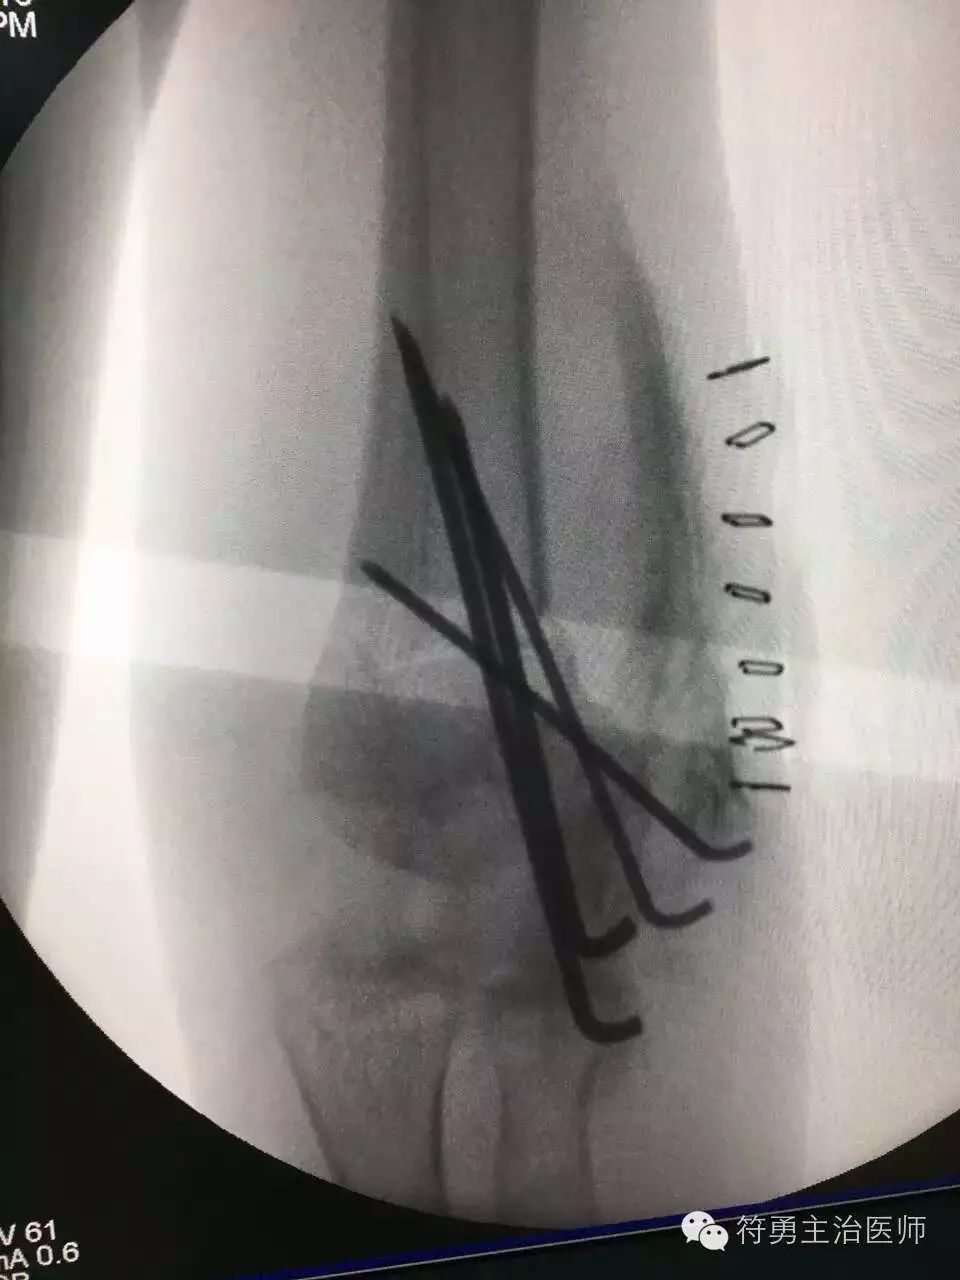

超级活波可爱的六岁男孩,人见人爱,因一年前不慎摔伤,导致左肘骨折,在外院未接受正规治疗,导致畸形愈合,严重肘内翻畸形,给孩子的父母和孩子的童年留下了阴影和遗憾,几经周折,找到我院小儿骨科,今日顺利接受截骨矫形手术,手术非常成功,小宝贝的胳膊恢复的跟正常一样!

成功的手术,驱散了孩子的童年阴影和心中的自卑,弥补了父母以前未带孩子去正规治疗而留在心中多年的遗憾与愧疚!